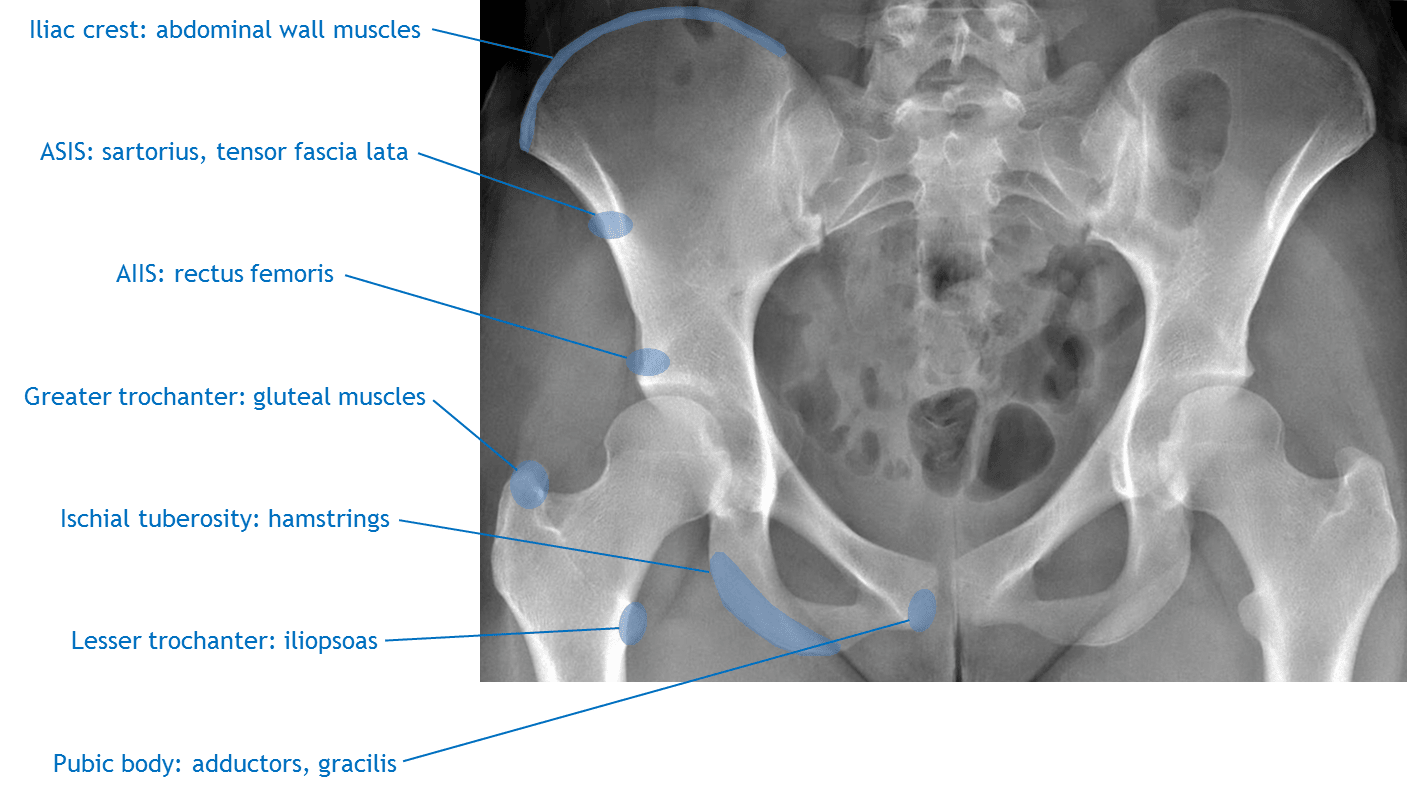

- Learn the major muscle and muscle group attachments on the anatomic pelvis (refer to first annotated image below)

Annotated Images & Illustrations

Sites of major muscle attachments on the anatomic pelvis.